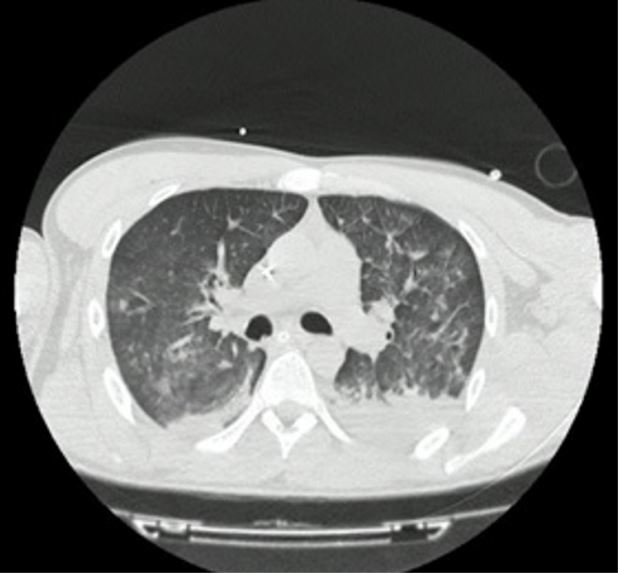

Por lo anterior, se trasladó el paciente a tomografía, donde se le realizó una imagen de tórax de alta resolución (figura 1), asociada con angiotomografía de cráneo, que evidenció un derrame pleural bilateral con patrón de empedrado. La imagen del cráneo no mostró cambios.

Frente a dichos resultados, se decidió trasladar al paciente a la unidad de cuidados intensivos para continuar el manejo médico con soporte ventilatorio. Por los hallazgos radiológicos de “vidrio esmerilado”, se le tomó la prueba de reacción en cadena de la polimerasa para SARS-CoV-2 en el contexto de pandemia, cuyo reporte fue negativo. Al ser valorado por el servicio de toxicología, este consideró que el cuadro, probablemente, se relacionaba con el consumo de cocaína. Luego de permanecer durante 48 horas con soporte ventilatorio, el paciente logró mejoría clínica, paraclínica y radiológica (figura 2), por lo que fue extubado sin complicaciones, con evolución favorable. Luego de ello se indicó su traslado a la unidad de hospitalización de psiquiatría, de donde egresó siete días después de su ingreso a urgencias.